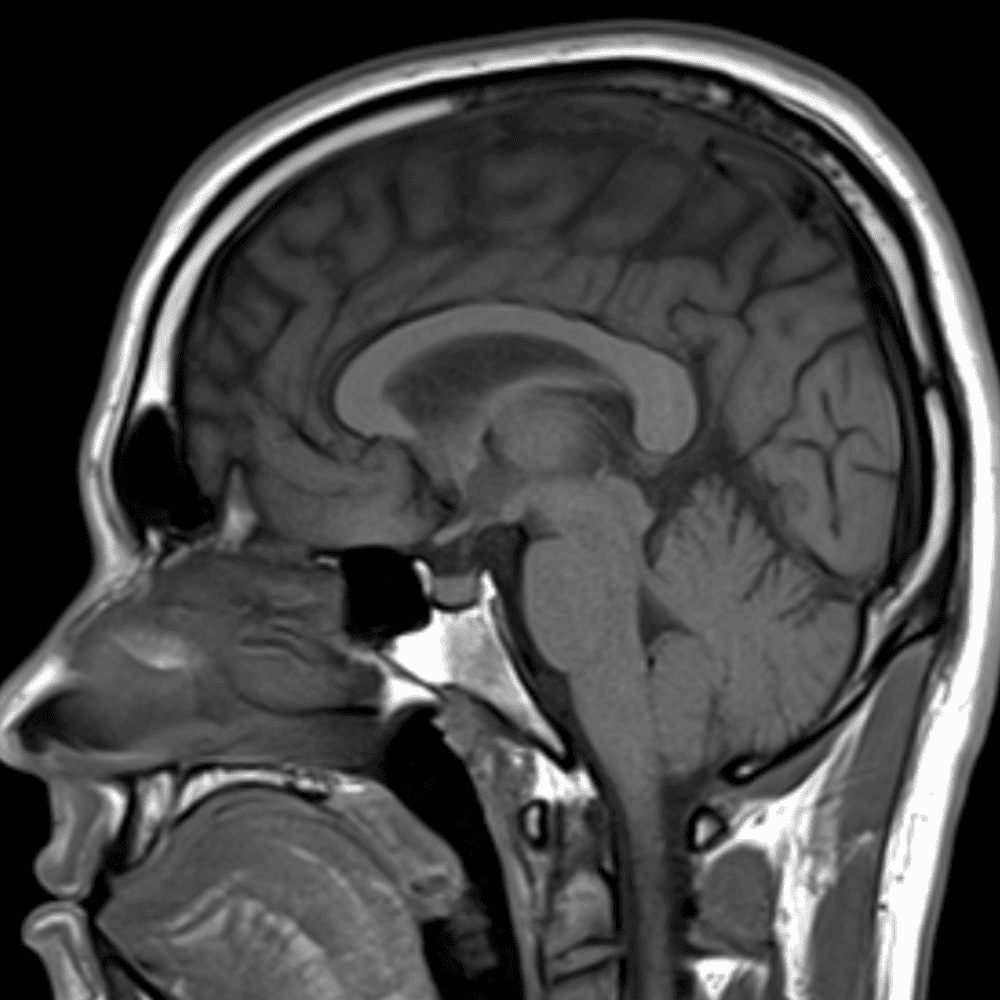

๋‹น์ง ์‹œ ํ”ํžˆ ๋ณผ ์ˆ˜ ์žˆ๋Š” ์‚ฌ๋ก€์˜ ์ „ํ˜•์ ์ธ ์˜ˆ๋ฅผ ํฌํ•จํ•ฉ๋‹ˆ๋‹ค.

39 ์‚ฌ๋ก€

์—ฐ์Šต

๋ฏธ๋ฌ˜ํ•˜๊ฑฐ๋‚˜ ์–ด๋ ค์šด ์‚ฌ๋ก€์™€ ์ผ๋ถ€ ์ •์ƒ ์‚ฌ๋ก€๋ฅผ ํฌํ•จํ•˜์—ฌ ๋‹น์ง์„ ์‹œ๋ฎฌ๋ ˆ์ด์…˜ํ•ฉ๋‹ˆ๋‹ค.

50 ์‚ฌ๋ก€